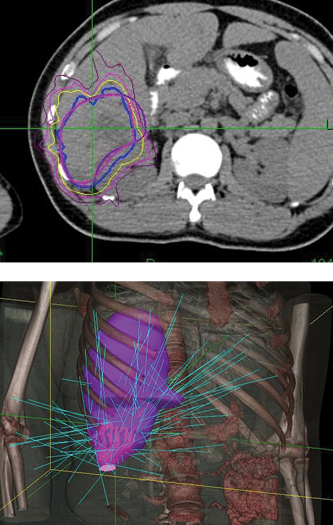

Phase 1 treatment covered the right lower lobe and hilar nodes, divided into two targets. The prescription was 48 Gy, delivered in four 12 Gy fractions for each of the two targets. Bilirubin fluctuations were noted during the course of therapy, but gradually returned to normal after treatment. One month after radiotherapy, a CT scan showed tumor shrinkage. The left lobe had sufficiently enlarged in compensation, so the second stage of treatment was initiated.

Phase 2 treatment covered the right upper lobe, divided into two targets: The prescription was 39 Gy, delivered in three 13 Gy fractions for each of the two targets.

“The patient lived more than two years with good quality of life after initial diagnosis, when life expectancy would have been one month without CyberKnife treatment.”